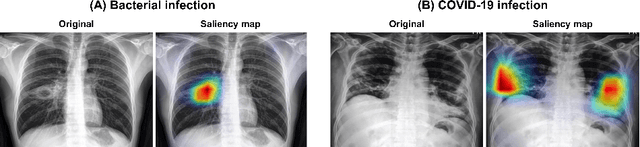

Abstract:Under the global pandemic of COVID-19, building an automated framework that quantifies the severity of COVID-19 and localizes the relevant lesion on chest X-ray images has become increasingly important. Although pixel-level lesion severity labels, e.g. lesion segmentation, can be the most excellent target to build a robust model, collecting enough data with such labels is difficult due to time and labor-intensive annotation tasks. Instead, array-based severity labeling that assigns integer scores on six subdivisions of lungs can be an alternative choice enabling the quick labeling. Several groups proposed deep learning algorithms that quantify the severity of COVID-19 using the array-based COVID-19 labels and localize the lesions with explainability maps. To further improve the accuracy and interpretability, here we propose a novel Vision Transformer tailored for both quantification of the severity and clinically applicable localization of the COVID-19 related lesions. Our model is trained in a weakly-supervised manner to generate the full probability maps from weak array-based labels. Furthermore, a novel progressive self-training method enables us to build a model with a small labeled dataset. The quantitative and qualitative analysis on the external testset demonstrates that our method shows comparable performance with radiologists for both tasks with stability in a real-world application.